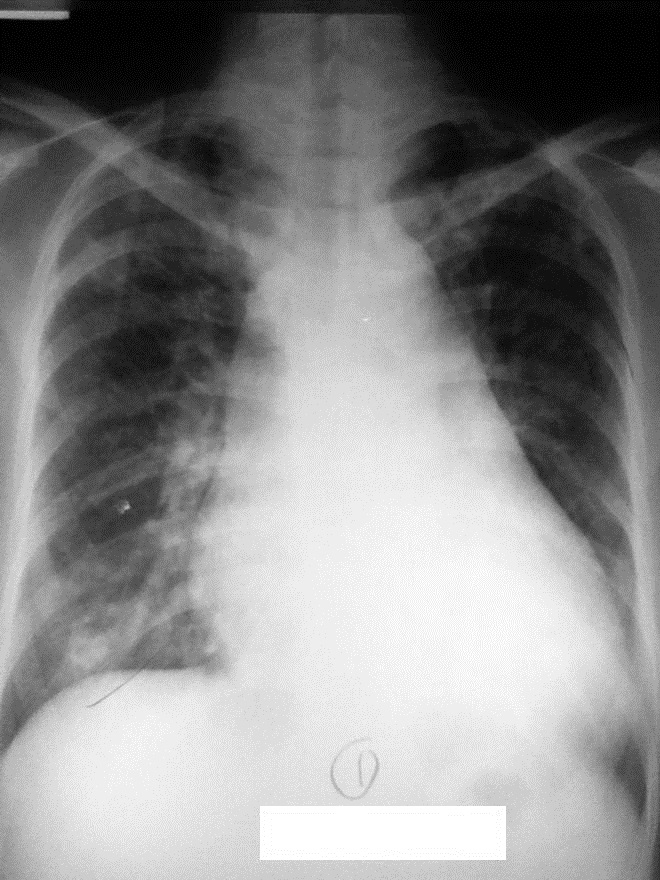

A 32-year-old Filipino woman on the 19th week of her fourth pregnancy presented at the emergency room with a seven-year history of diffuse goiter associated with tremors, palpitations, heat intolerance, exophthalmos and exertional dyspnea. Prior to this consult, she was previously taking anti-thyroid medications which were discontinued five years ago upon improvement of symptoms, and was subsequently lost to follow up. On admission, the patient was febrile, tachycardic in atrial fibrillation, hyperreflexic, with fine finger tremors. Ophthalmologic examination revealed positive Dalrymple's, Kocher's, and Von Graefe's signs, lagophthalmos, chemosis and periorbital edema. The thyroid gland was non-tender and diffusely enlarged, measuring 5x5 cm per lobe. Auscultation revealed bibasal fine crackles, and there was note of hyperpigmented, non-pitting induration over the pretibial area of both legs, clubbing of the fingers and pedal edema. She was treated for Graves' disease in thyroid storm, with congestive heart failure from thyrotoxic heart disease. Her chest radiograph showed left ventricular cardiomegaly (Figure 1). She improved with propylthiouracil, propranolol and furosemide and was discharged.

Click here to download Figure 1Figure 1.Chest radiograph taken on postero-anterior view during initial admission showing left ventricular cardiomegaly with pulmonary congestive changes.